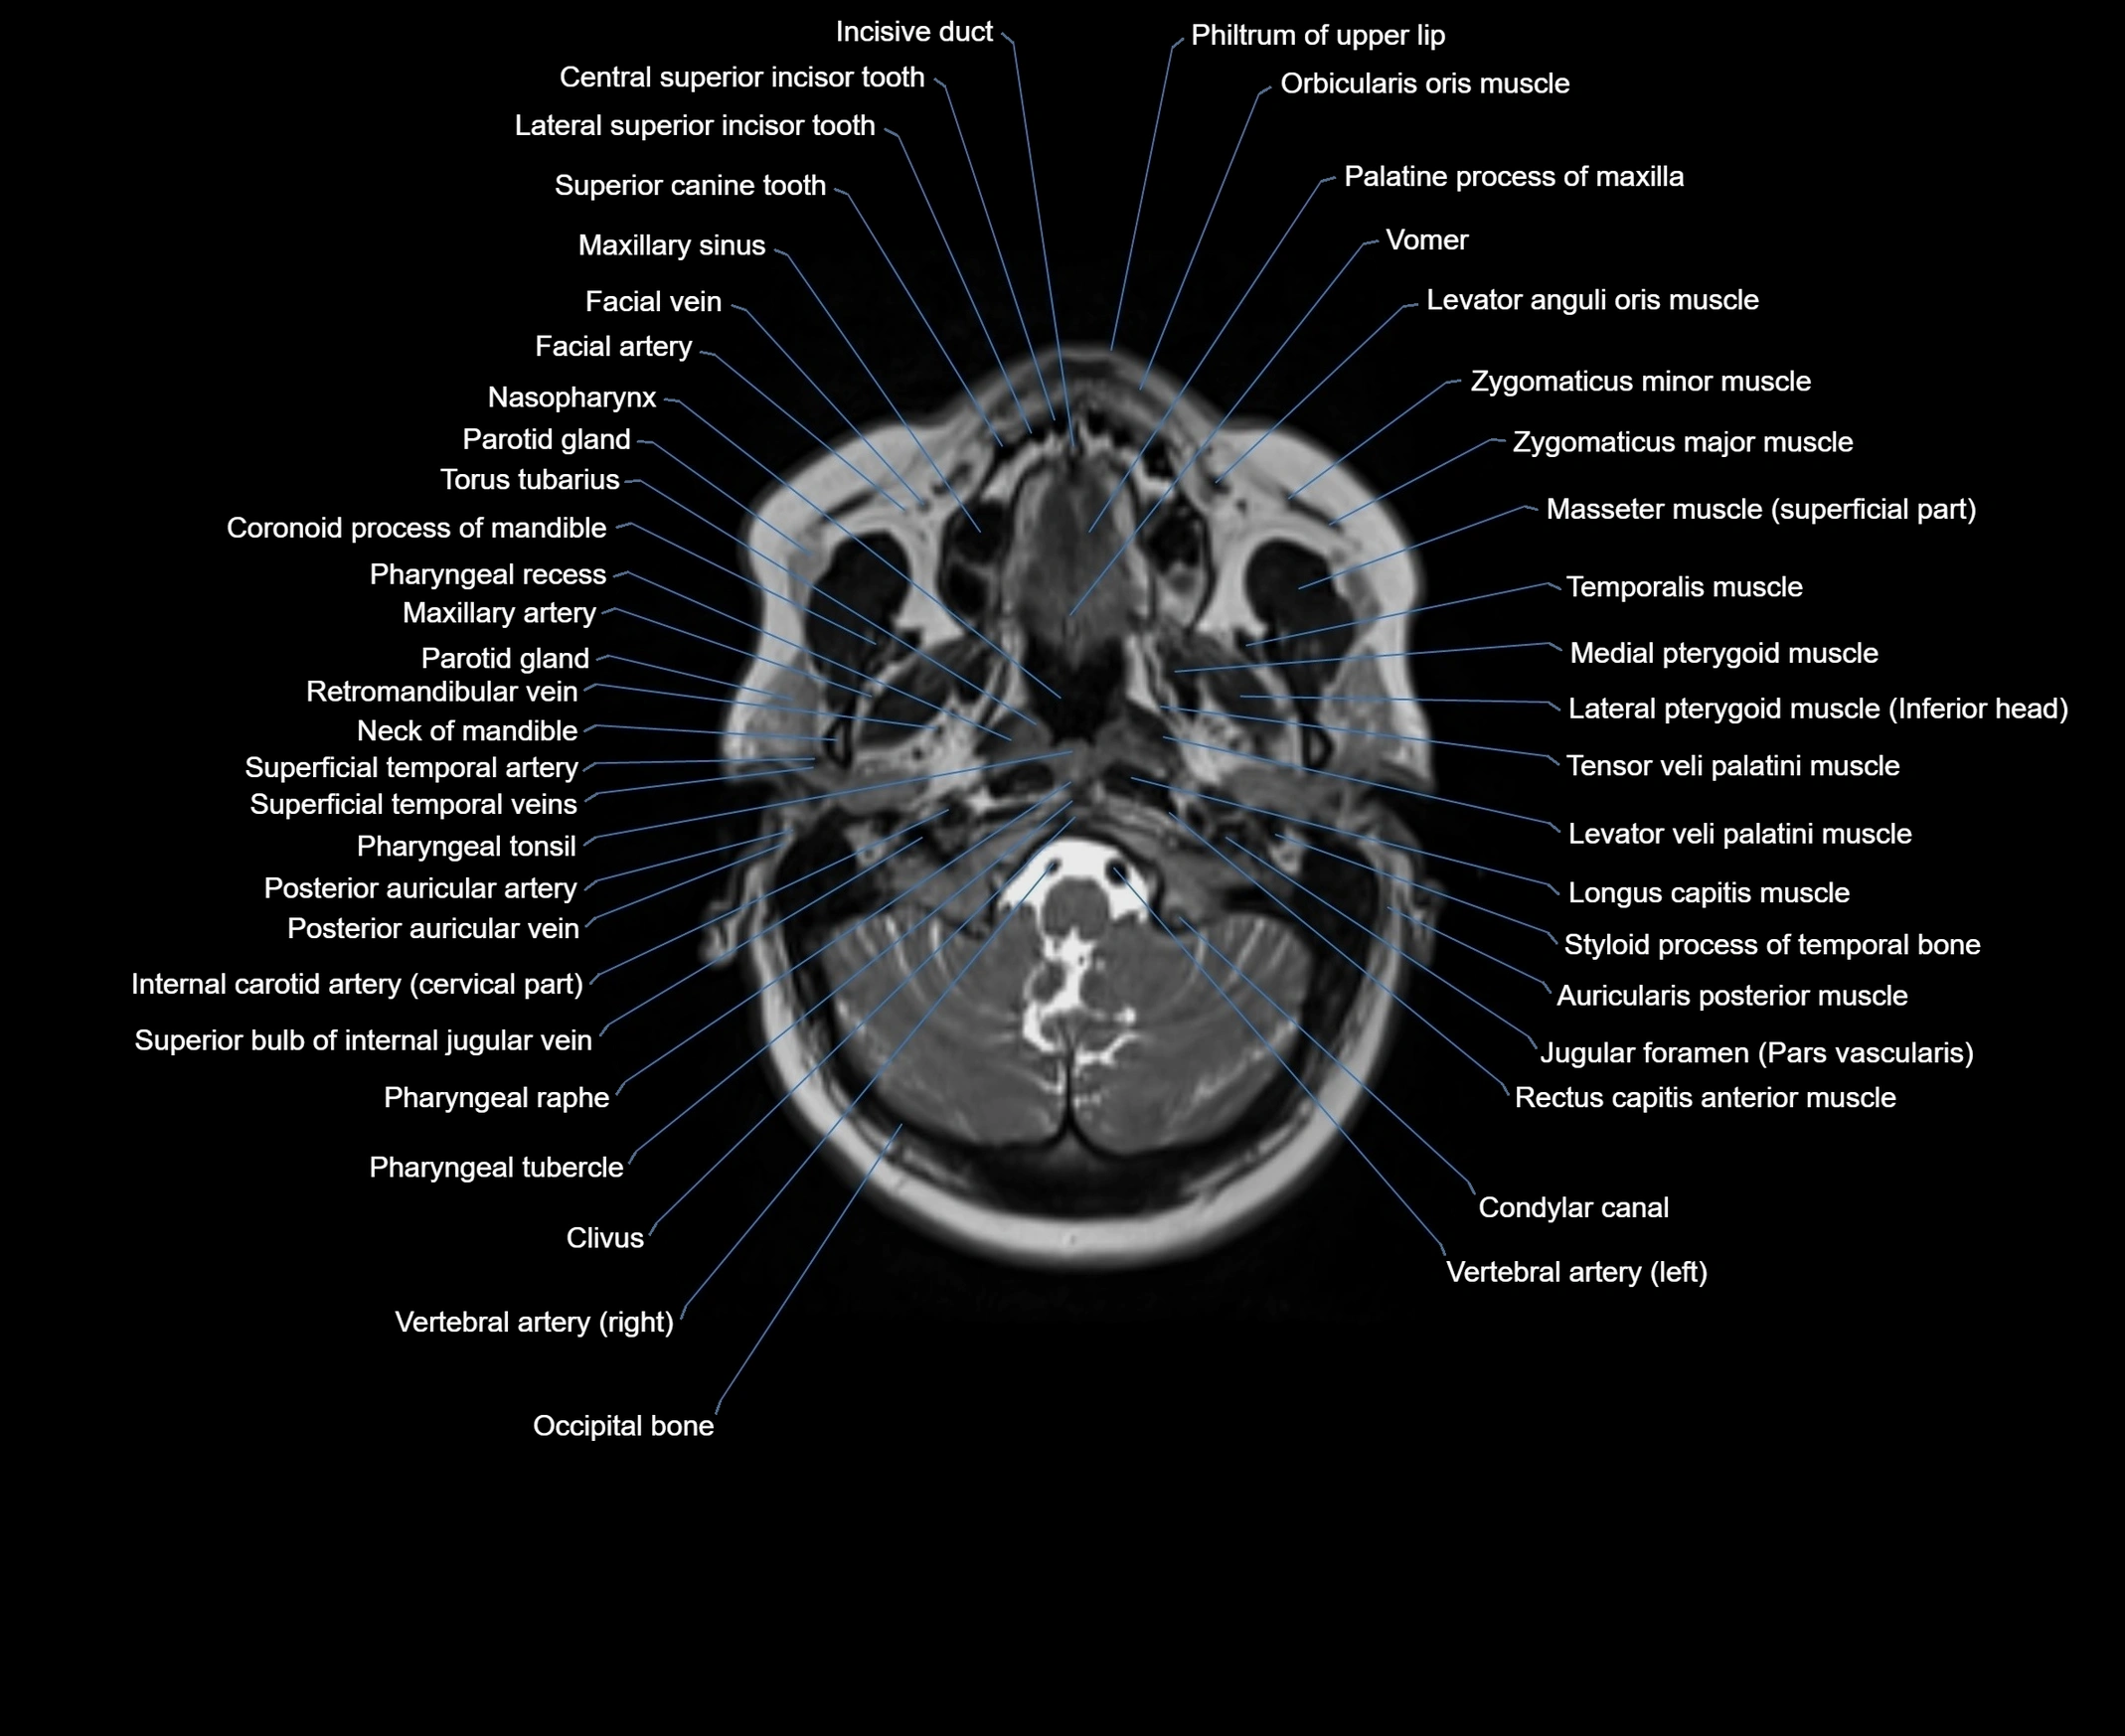

- Condylar canal

- Incisive duct

- Internal carotid artery (cervical part)

- Jugular foramen pars vascularis

- Longus capitis muscle

- Nasopharynx

- Occipital bone

- Occipital condyle

- Pharyngeal raphe

- Pharyngeal recess

- Pharyngeal tonsil

- Pharyngeal tubercle

- Posterior auricular artery

- Posterior auricular vein

- Superior bulb of internal jugular vein